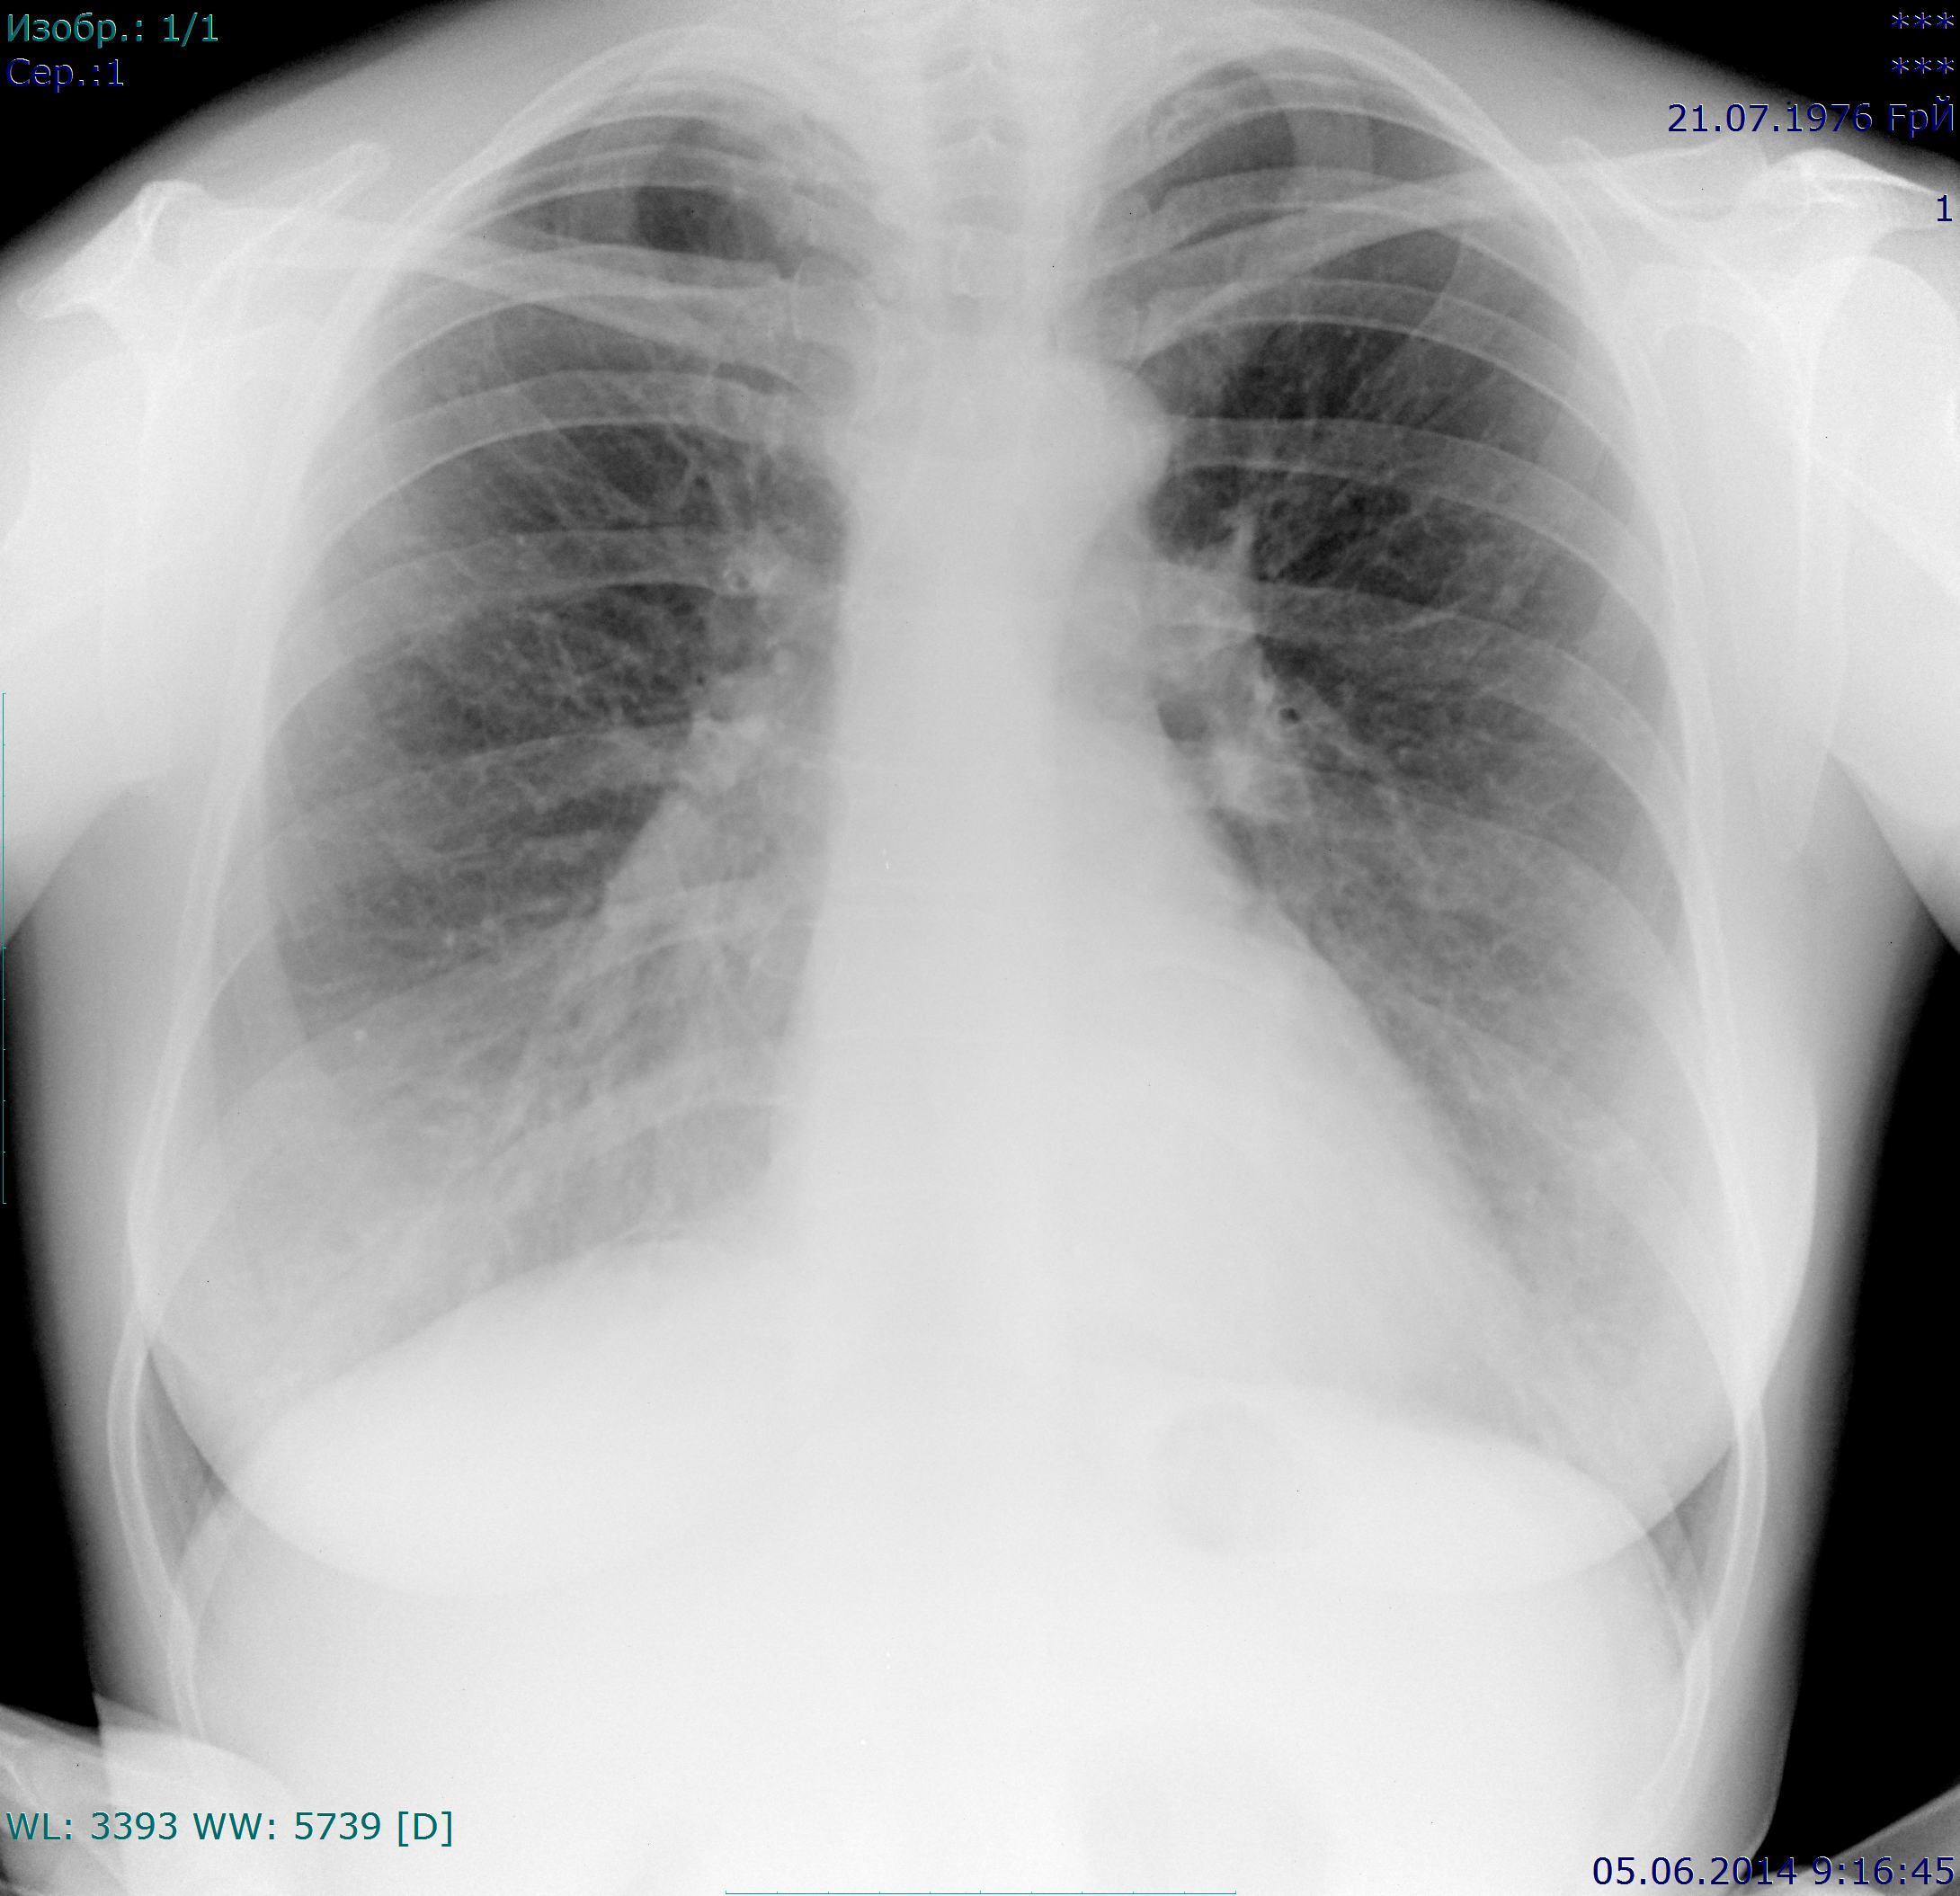

Если можно, довеском. Пациентка 1976 г.р., жалоб нет, проф флг. Требует ли дообследования тень в проекции 3 р слева? Последний - архив 2009г.

Выскажусь пока только по второму. Очаговая тень появилась.На архивном снимке её не было. Поэтому : или дообследование, или хотя бы заднюю проекцию (с отведенными лопатками) стоит доделать

№ 1 скорее да, доля v.azygos, № 2 норма -сосуд,разница в установке.

Может и сосуды, а может и нет (крупновато). Я с такими тенюшками, выявленными впервые, предпочитаю разобраться, чем потом меня, как плохого котёнка , будут носом тыкать в моё..... и интересоваться, куда ж я смотрела.

А здесь в 1 м/р слева - сосуд?

Это может быть плотным очагом или эностозом в заднем отрезке V ребра. Эта тень интенсивная. Тревоги не вызывает.